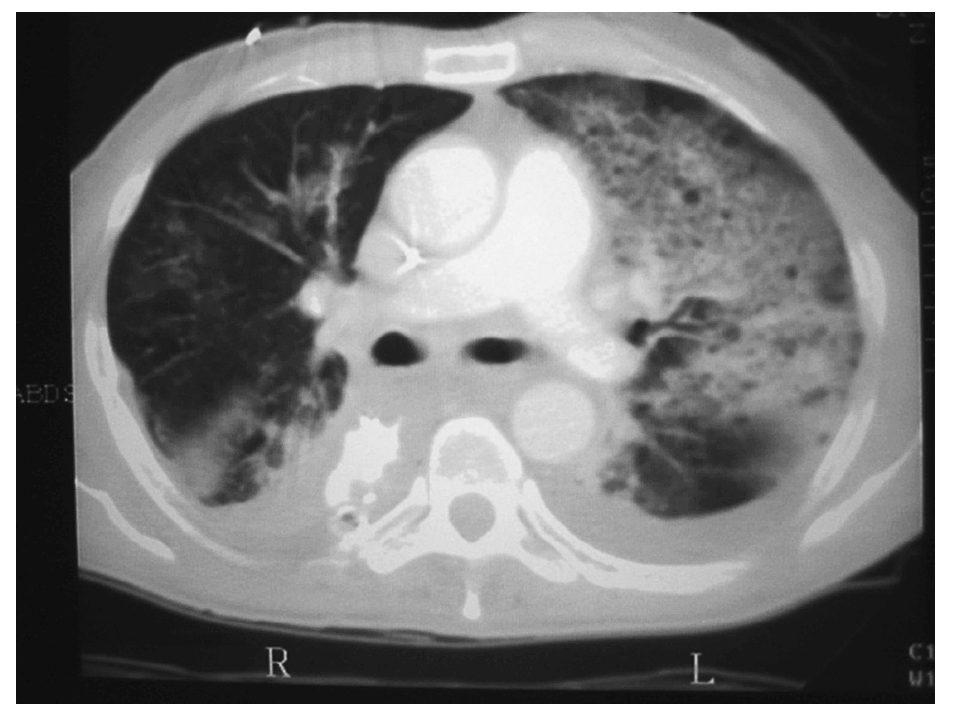

La neumonía asociada a ventilación mecánica (NAVM) es un tipo específico de neumonía nosocomial que pueden desarrollar los pacientes que están en ventilación mecánica más de 48 h de manera continuada. Su incidencia es del 1% por día durante el primer mes de ventilación. Se desarrolla como consecuencia de la traslocación bacteriana, la alteración de la función gastrointestinal y la aspiración de secreciones contaminadas con organismos patógenos que parecen adquirirse por vía endógena. Estos patógenos alcanzan la vía distal mediante el reflujo y aspiración mecánica de contenido gástrico contaminado y también mediante la inoculación repetitiva de secreciones de la vía aérea superior hacia el árbol traqueobronquial distal. Suele ser polimicrobiana (Pseudomonas aeruginosa, Acinetobacter spp. y S. aureus). El diagnóstico de la NAVM puede ser difícil (figs. 2 y 3), ya que otras causas de fiebre e infiltrados pulmonares, como las atelectasias y la lesión pulmonar aguda (LPA)28, pueden entrar en el diagnóstico diferencial.

Fig. 2. Radiografía de tórax de un paciente intubado y con ventilación mecánica en el quinto día del postoperatorio. Infiltrado alveolar con broncograma aéreo en prácticamente todo el pulmón izquierdo compatible con bronconeumonía.

Fig. 3. Tomografía computarizada del mismo paciente de la imagen anterior. En el pulmón izquierdo se puede observar infiltrados alveolares compatibles con proceso de consolidación neumónica junto con pequeños derrames pleurales bilaterales posteriores.